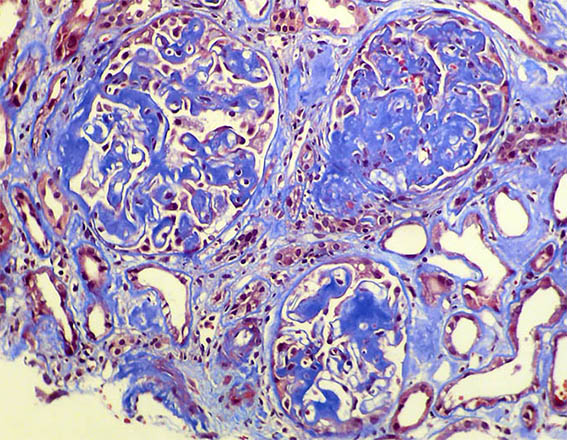

A 33-year-old man presented with pedal edema, persistent proteinuria and hypertension. Her past and family histories were unremarkable. Her blood pressure was 160/100 mm Hg. Physical examination revealed pedal and facial edema, without other alterations. Laboratory tests showed proteinuria of 4.7g/24 h, serum creatinine 1,0 mg/dL, microhematuria, normal serum complement levels, ANA negative; HIV, hepatitis B and C viral infections were negative. Ultrasound of the abdomen showed normal sized kidneys.

Kidney biopsy was performed. Look at the images.

Figure 3.

Masson's trichrome stain, X200.